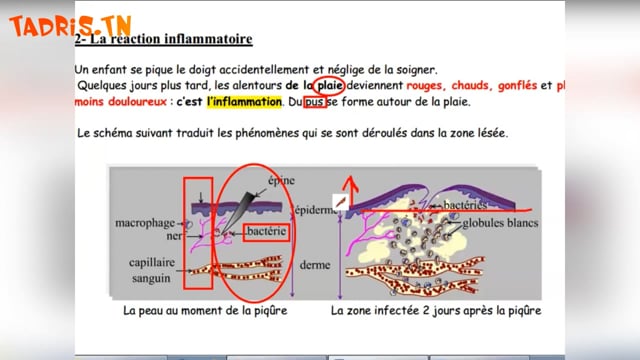

Sciences SVT